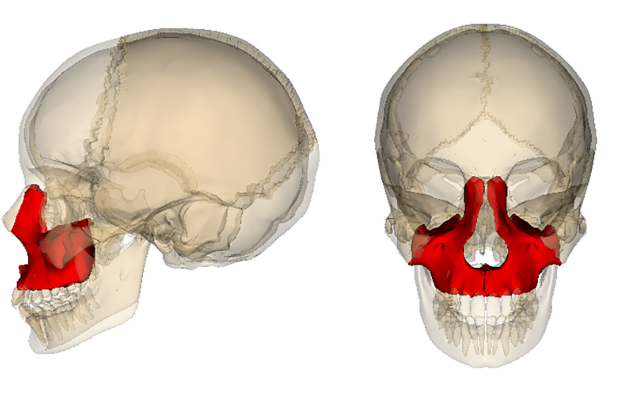

Is it possible to move the maxilla forward at 12-15 years old? Without special braces or anything, just thumb pulling.

js get marpe if ur pallette is narrowIs it possible to move the maxilla forward at 12-15 years old? Without special braces or anything, just thumb pulling.View attachment 4360479

mewing is proper tongue posture but doesn't do too muchIs it possible to move the maxilla forward at 12-15 years old? Without special braces or anything, just thumb pulling.View attachment 4360479